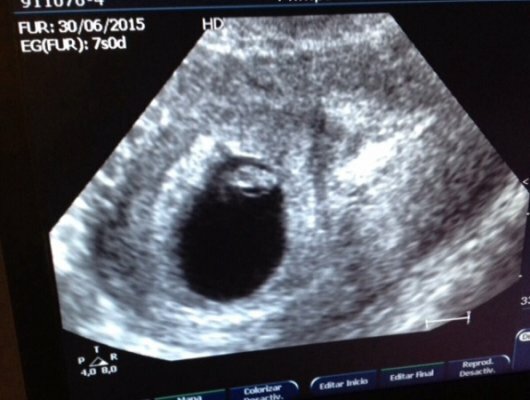

Primera etapa

El cigoto es la primera etapa del periodo prenatal y comprende desde la concepción hasta las dos semanas de edad